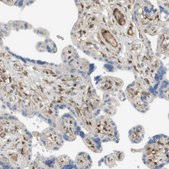

immunoblotting: 0.04-0.4 μg/mL, immunofluorescence: 0.25-2 μg/mL, immunohistochemistry: 1:200-1:500

The Human Protein Atlas project can be subdivided into three efforts: Human Tissue Atlas, Cancer Atlas, and Human Cell Atlas. The antibodies that have been generated in support of the Tissue and Cancer Atlas projects have been tested by immunohistochemistry against hundreds of normal and disease tissues and through the recent efforts of the Human Cell Atlas project, many have been characterized by immunofluorescence to map the human proteome not only at the tissue level but now at the subcellular level. These images and the collection of this vast data set can be viewed on the Human Protein Atlas (HPA) site by clicking on the Image Gallery link. We also provide Prestige Antibodies® protocols and other useful information.

- IHC tissue array of 44 normal human tissues and 20 of the most common cancer type tissues.